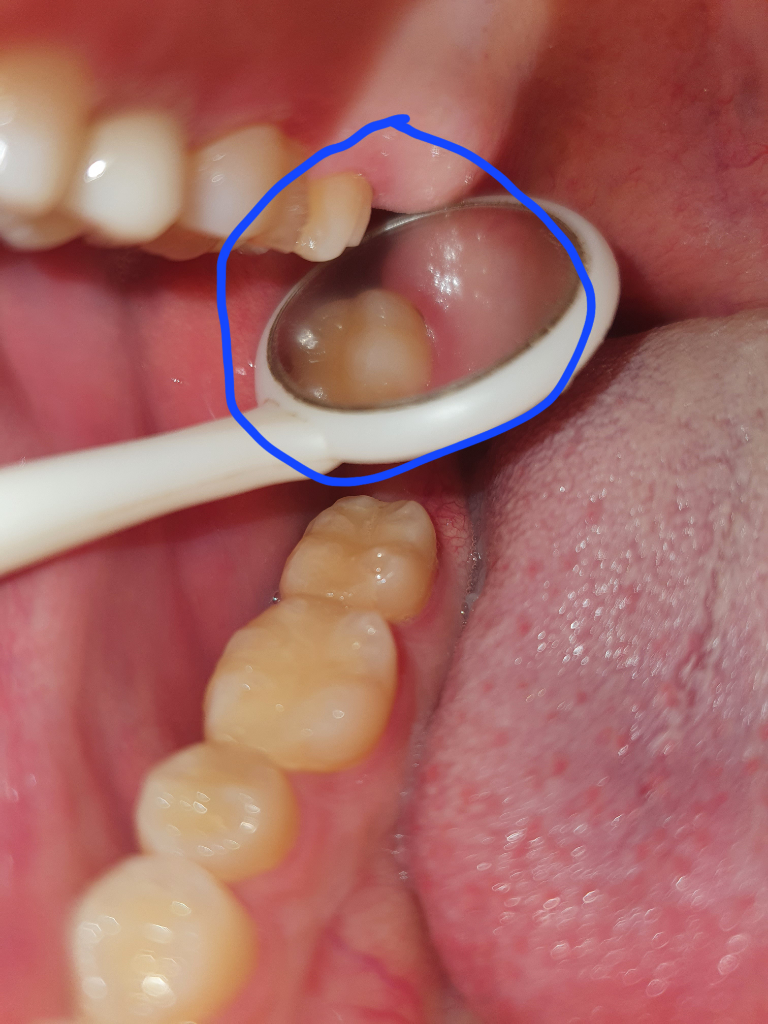

윗 어금니 잇몸사이에 검은선 충치인가요?

윗 사랑니를 뽑고난후 너무시려서 어금니를 확인하니

어금니와 잇몸이 만나는 곳에 조그만하게 검은선이 보입니다.

따로 치간 칫솔같은걸로 닦거나 건드려봐도 사라지지 않고있습니다.

의사선생님이 이빨이 시린건 사랑니 발치 때문이라고 하기도 하셨고 발치전에 스케일링도 받았었는데 어금니에 충치있다고 말씀해주시진 않으셨는데 혹시 이거 충치일까요?

• 1번 째 사진

현재 사진 상으로는 충치로 보기는 어려우며 보다 정확한상태한 파악을위해 빠른 시일내에 치과를 방문하여 진료를 받으시길 권장드립니다.

살짝 충치가 잇는걸수도 있고, 그쪽에 착색이 됫을수도 있습니다. 사랑니 뺄때 치과의사선생님께서 별말씀없으셧다면 충치는 아니고, 만약 저게 충치라고 해도 지켜보면서 관리하시면 크게 이상은 없으실꺼에요.

충치일 가능성도 있고,

잇몸쪽에 치석이 있는것일 수도 있습니다.

현재 찍힌 사진의 각도만으로는 판단하기가 상당히 어렵습니다. 따라서 치과 방문 후 확인이 필요하며 충치가 아니라 잇몸과 치아 사이의 경계가 떠서 검게 보일 수도 있습니다. 개인적인 소견으로는 아닐 가능성이 있어 보이며 보통 사랑니와 어금니가 인접하게 되면 지금과 같이 발치 이후에 시리거나 통증 등이 나타날 수 있으나 대부분 시간이 지나면 회복됩니다.

사진으로만 봐선 정확하진 않지만 충치같아보이진 않습니다.